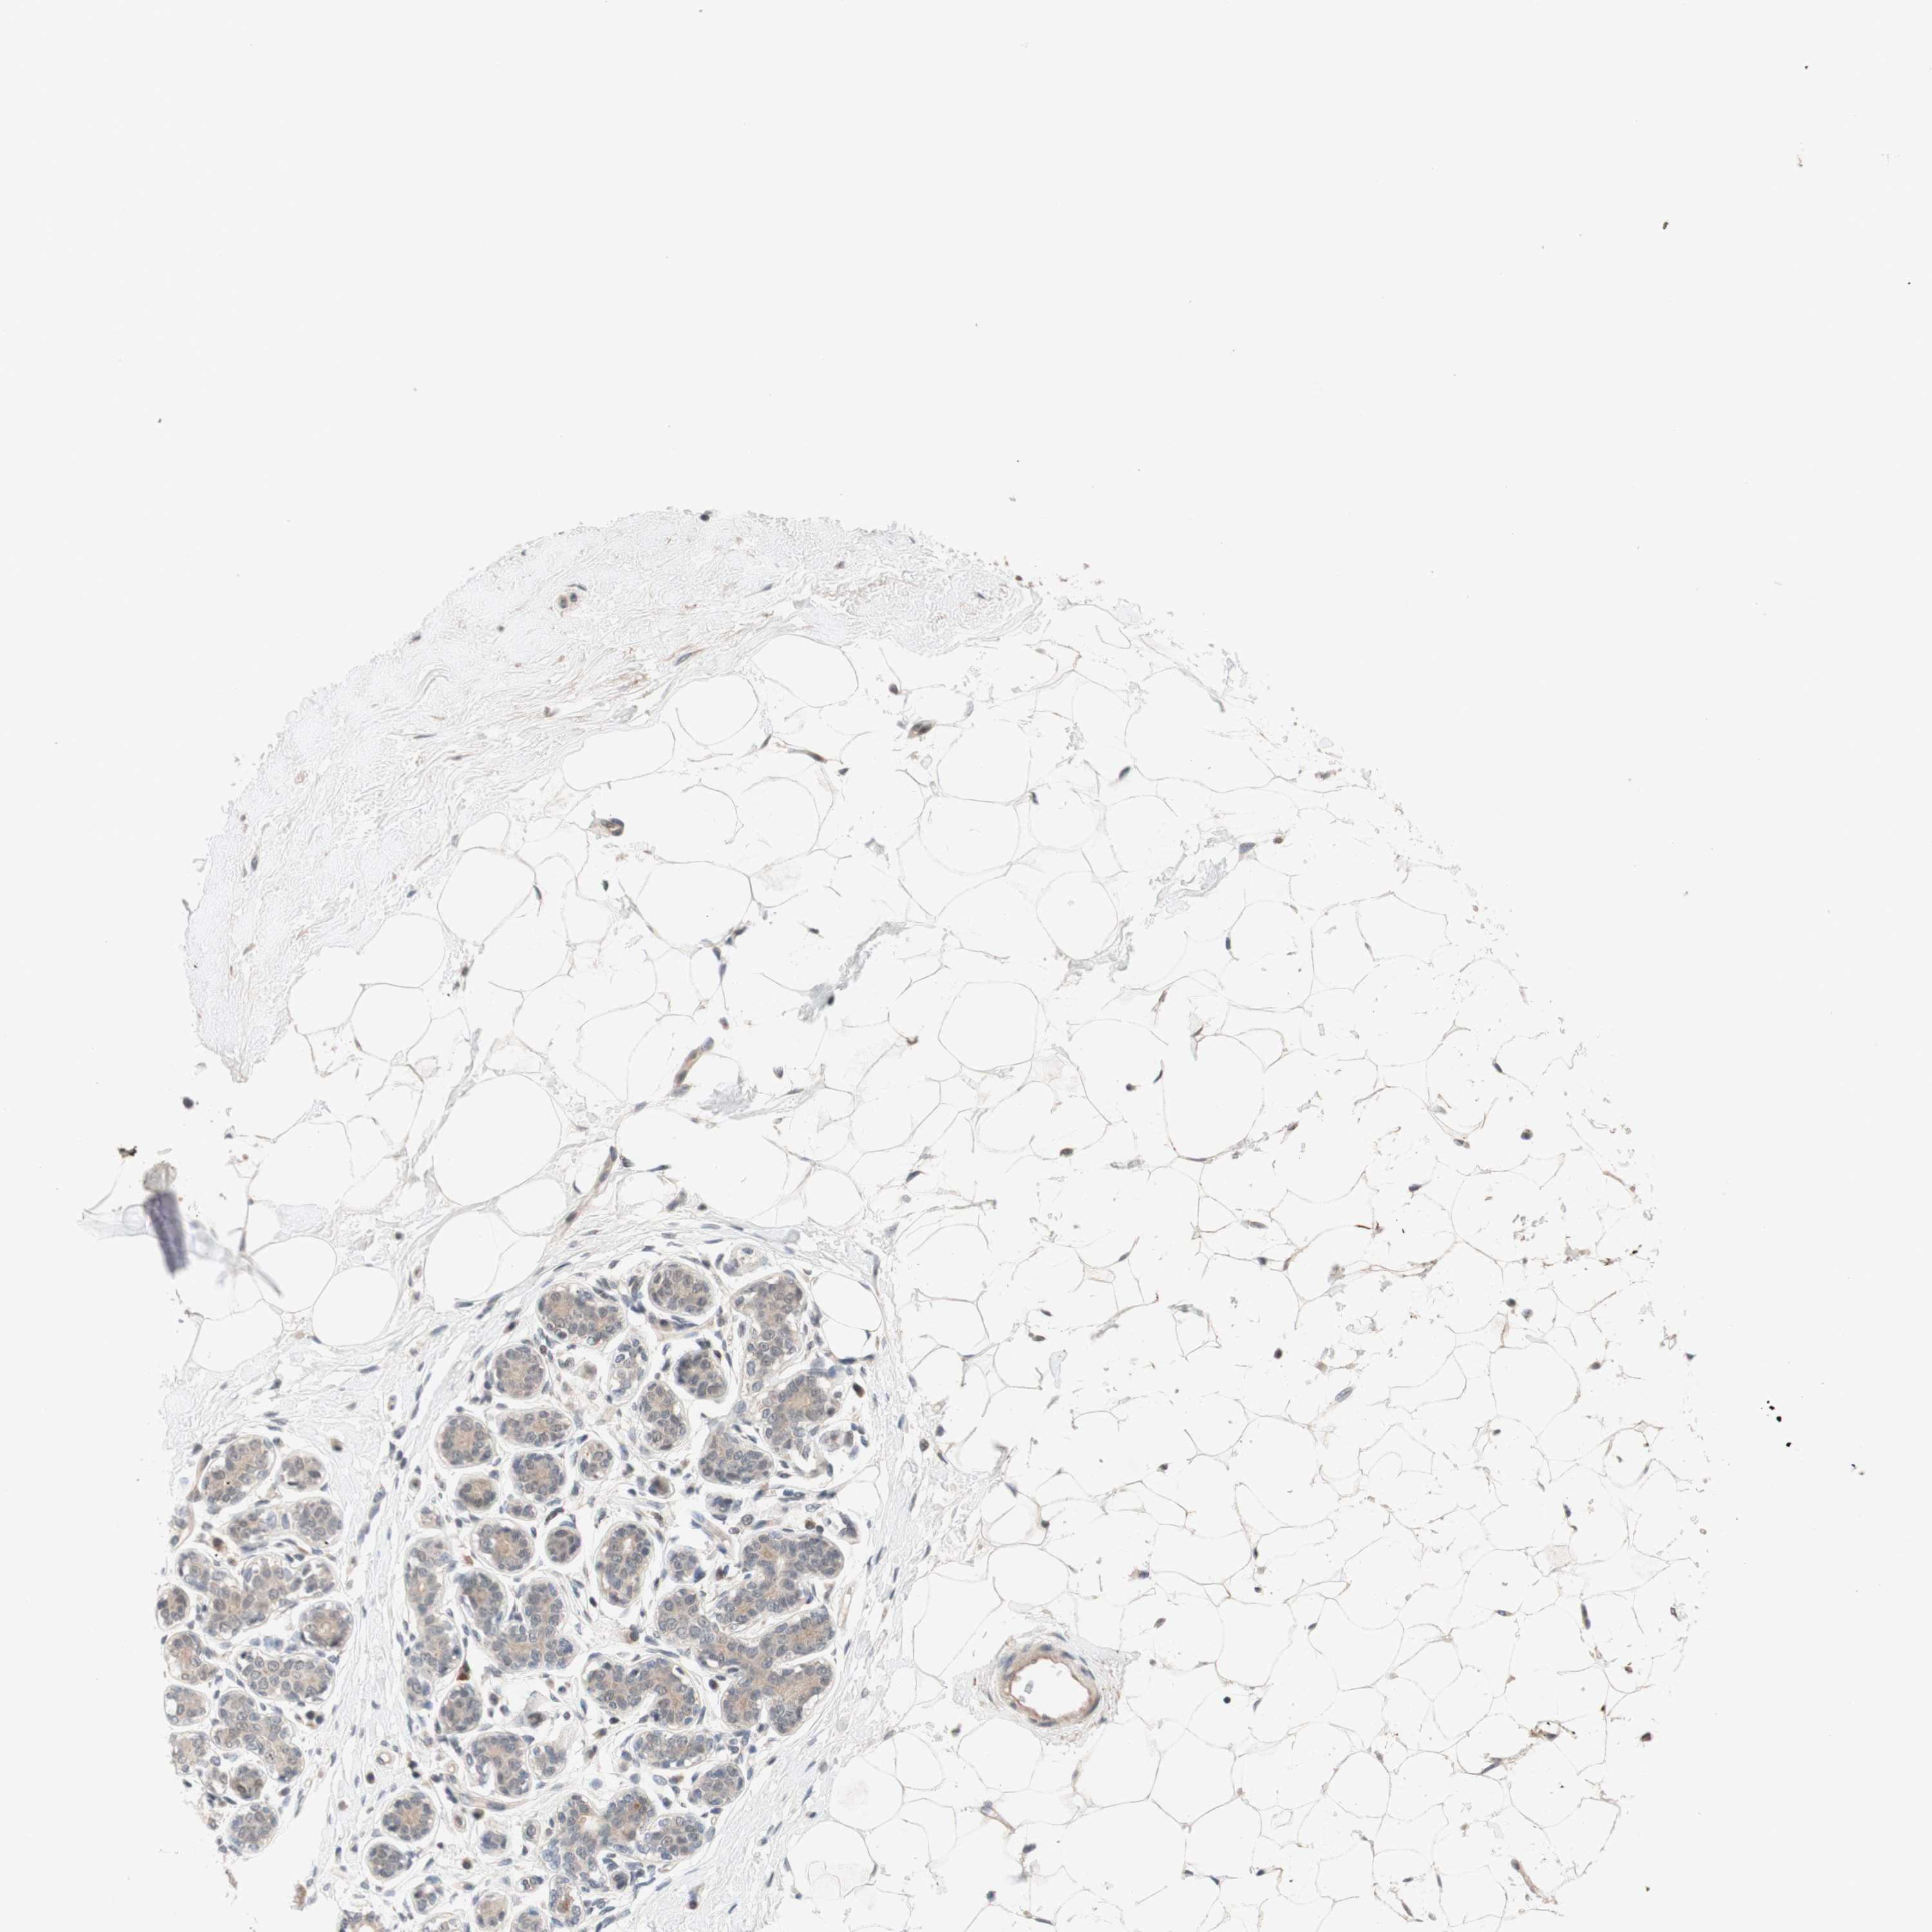

BRCA TCGA BRCA VALIDATION PROTEIN EXPRESSION

ANTIBODIES

AND

VALIDATION